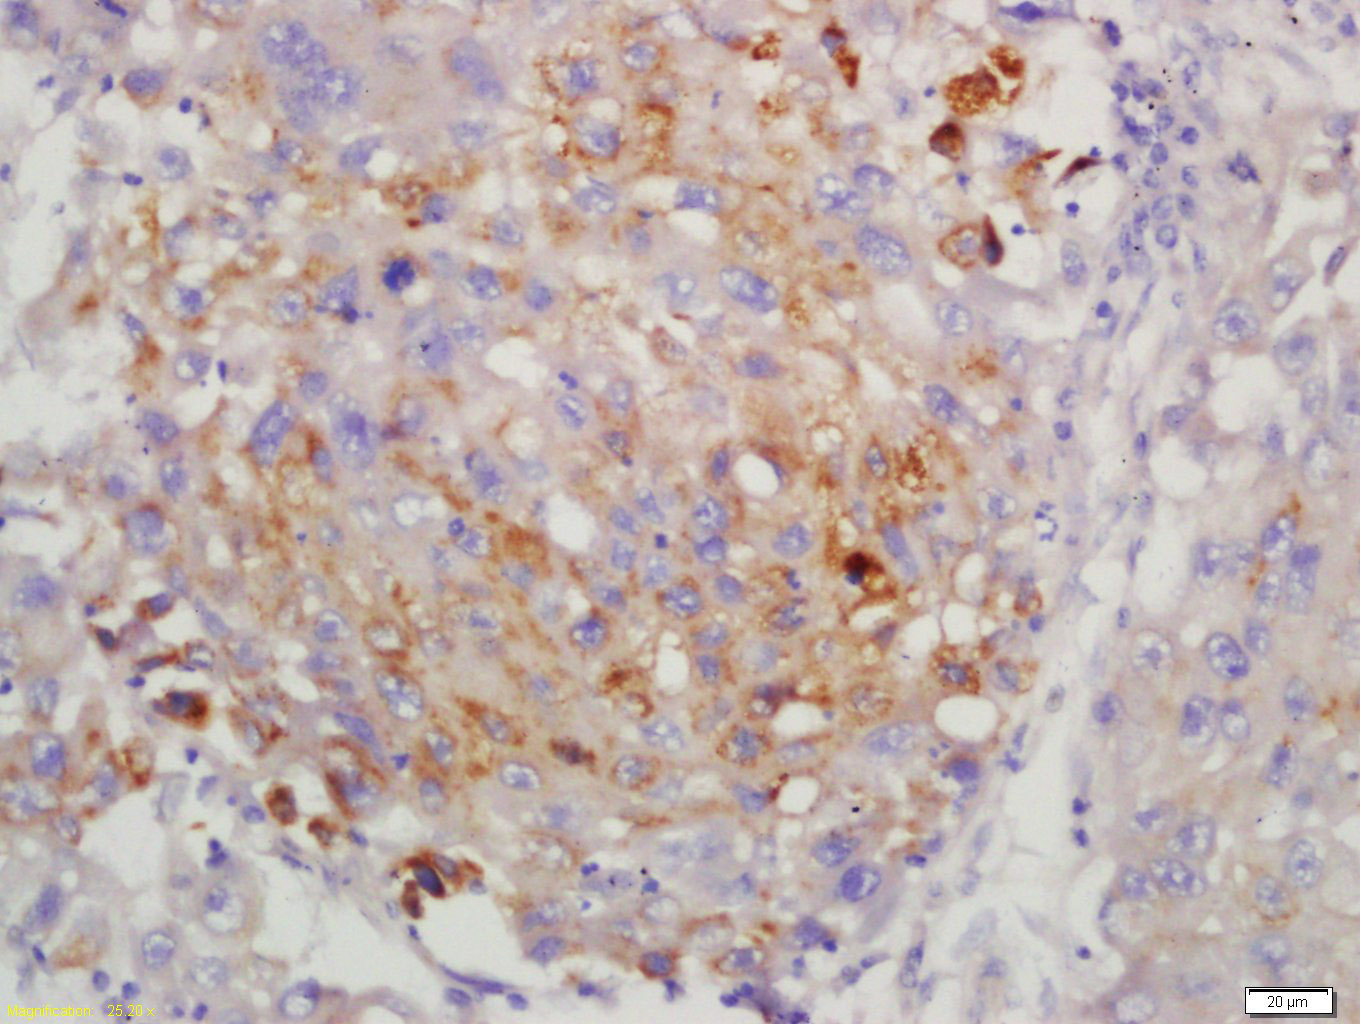

Antigen retrieval: citrate buffer ( 0.01M, pH 6.0 ), Boiling bathing for 15min; Block endogenous peroxidase by 3% Hydrogen peroxide for 30min; Blocking buffer (normal goat serum,C-0005) at 37℃ for 20 min;

Incubation: Anti-LMP7 Polyclonal Antibody, Unconjugated(bs-2796R) 1:200, overnight at 4°C, followed by conjugation to the secondary antibody(SP-0023) and DAB(C-0010) staining